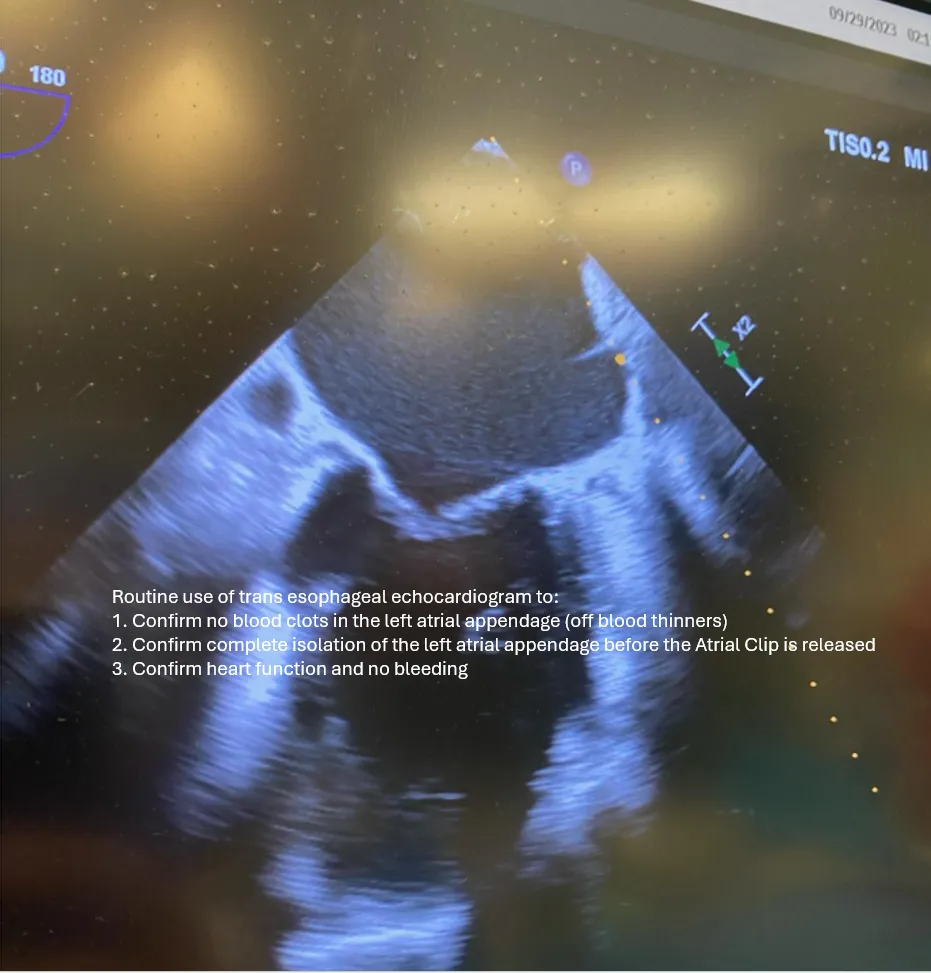

Many patients may qualify to discontinue blood thinners after rhythm stabilization and secure management of the left atrial appendage. This decision is individualized based on your stroke risk score (CHA₂DS₂-VASc), imaging, and shared decision-making with your cardiologist.